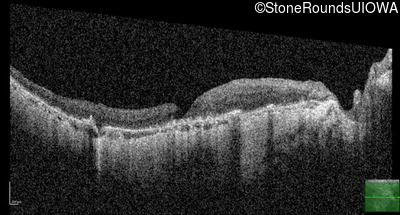

This 81 year old man began using a flashlight to read menus in his 40's. At age 75 his ophthalmologist noticed abnormal fundus findings and referred him to a retina specialist.

| Age at visit: 81 years |

| Age at visit: 82 years |

| Age at visit: 83 years |

| Age at visit: 84 years |

| Age at visit: 85+ (Visit 1) |

| Age at visit: 85+ (Visit 2) |